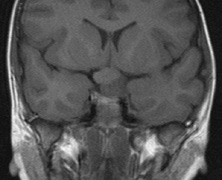

CNS hemangiomas are the most common tumor of VHL, affecting 60% to 80%, with a predilection for the cerebellum and spinal chord. An enlarging cystic component is a frequent finding in symptomatic tumors. Patients typically present in their early 30s; headaches or neck pain in affected individuals should not be ignored.172,173 On microscopy, CNS hemangiomas resemble retinal capillary hemangiomas. Their malignant potential is low.174 The treatment is surgical (Fig. 17, A and B).13

Fig. 17. Images from a 13-year-old boy with Von Hippel-Lindau syndrome. (a) Coronal postcontrast T1-weighted imaging reveals a cystic lesion with an enhancing nodule at the pial surface typical of a hemangioblastoma. (b) A second solid enhancing hemangioblastoma is seen at the craniocervial junction on a sagittal postcontrast T1-weighted image. (c) Associated cystic lesions (arrows) are seen within the pancreas.